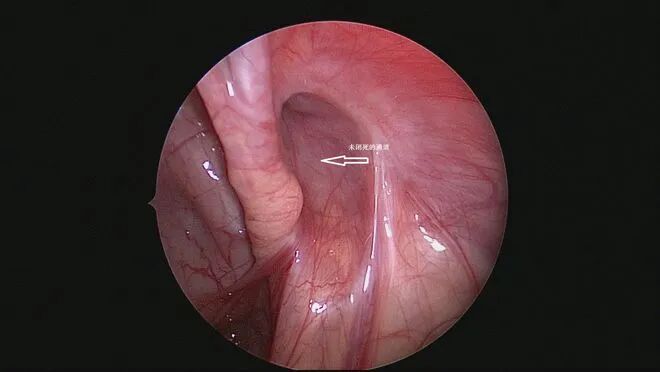

原因在于鞘狀突沒有正常閉合。鞘狀突是一種位于腹股溝區(qū)域的通道,它在我們還是胎兒的時候起著連接睪丸和腹膜的作用。隨著我們的成長,大多數(shù)人的鞘狀突會自然閉合,但有些小朋友的鞘狀突卻留了下來,這就可能導(dǎo)致鞘膜積液的問題。

腹腔鏡是一個帶有攝像頭的工具,可以幫助醫(yī)生清晰地看到鞘膜囊的情況。

在手術(shù)過程中,醫(yī)生會小心地將鞘膜囊找到,并使用特殊的線將其結(jié)扎。這個過程就像是我們用線將“小腫塊”的口扎緊一樣,確保里面的水不會輕易流出來。